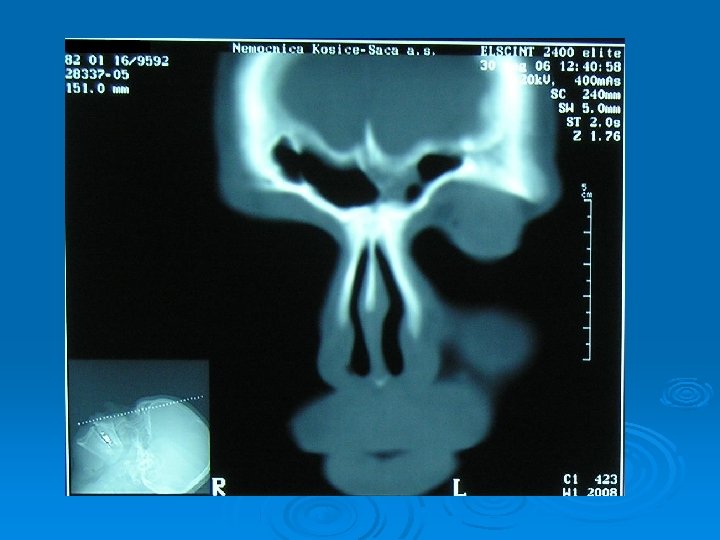

Kazuistika č. 2 – 35 ročný pacient R. Š. Subj: 3 -4 mesiace únava, bolesti hlavy, pocit tlaku, prekonal boreliózu, alergia na pele a prach CT PND: odliatkový osteóm ľavej čelovej dutiny Op. liečba: osteoplastická frontálna sinusotómia vľavo Histológia: Osteoid osteoma